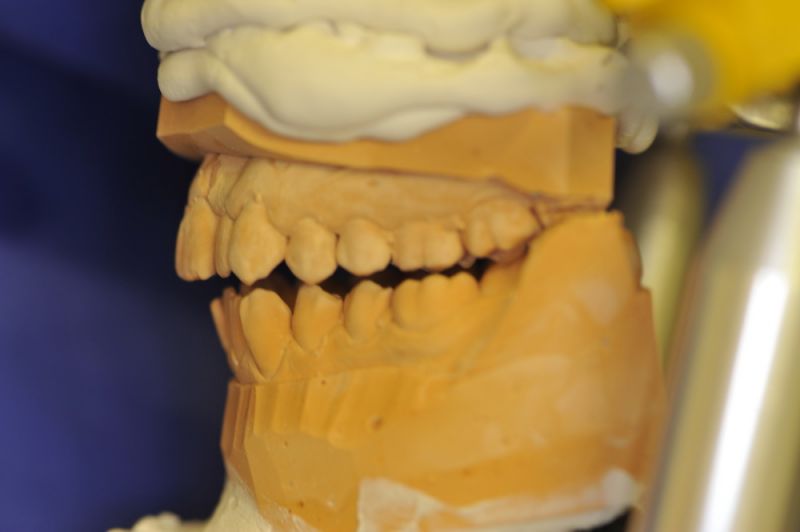

Extreme Dysgnathie einer Patientin aus Kiel mit Aufbissbehelf vollkommen beschwerdefrei

Die Patientin trägt den Aufbissbehelf seit dem 18.09.2014 und ist nach einem Beschwerdelevel "10" vor der Eingliederung des Aufbissbehelfs inzwischen bei Beschwerdelevel "0". Die Patientin kann den Aufbissbehelf auf Grund der "Sperrigkeit" des Geräts bei der Arbeit nicht tragen. Wenn sie den Aufbissbehelf heraus nimmt kommen die Beschwerden nach wenigen Stunden zurück. Wenn sie die Arbeit beendet hat und den Aufbissbehelf einsetzt dauert es ca. 15 Minuten bis wieder Beschwerdefreiheit erreicht ist.